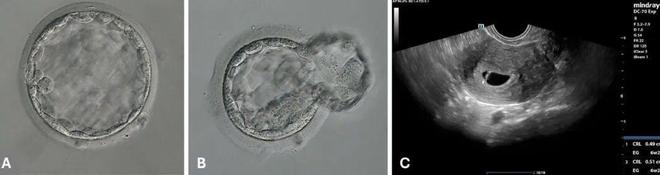

在其中一个步骤中,系统会利用 AI 技术根据精子细胞的外观挑选出最健康的精子细胞以用于受精。机器还会通过使用激光照射精子的尾部来使其无法移动,以便更容易地收集精子。随后,系统会将精子注入已采集的卵子中。在这一自动系统中,5 枚注射卵中有 4 枚实现了正常受精,手动对照组中有 3 枚实现了正常受精。

然后,该公司利用 AI 根据胚胎染色体的外观挑选出两个最佳的胚胎。这两种胚胎都是通过自动化系统培育的,但这并不一定意味着这种方法培育出的胚胎比人工卵胞浆内单精子注射培育出的胚胎更健康。由于涉及的卵子数量较少,因此当时 Conceivable 公司无法对此进行评估。而当将其中一枚胚胎植入该女性子宫时胚胎未能发育,但第二个胚胎获得了成功。最终,一个在培养中发育至囊胚阶段的高质量胚胎,通过这种远程控制的自动化系统完成了受精。随后,这个囊胚在后续周期中被移植,接着这名女性成功实现了妊娠,并顺利分娩出一名健康男婴。通过捐赠卵子治疗以及使用该公司的技术,这名女性终于得以成为一名母亲。